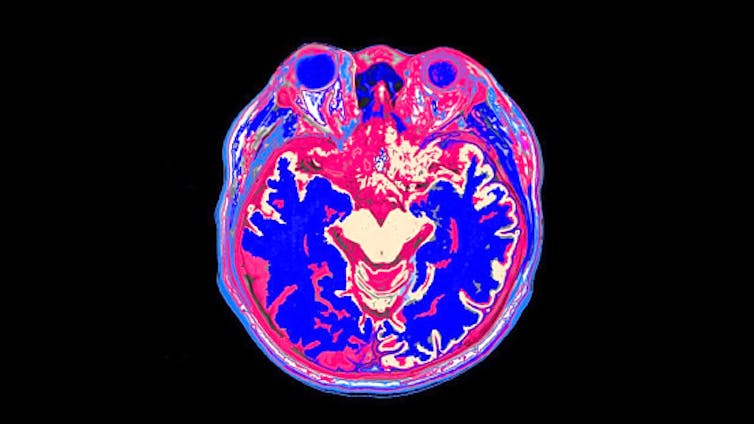

My colleagues and I use brain scans like this MRI to study what the brain is doing when a person reads.

Rajaaisya/Science Photo Library via Getty Images